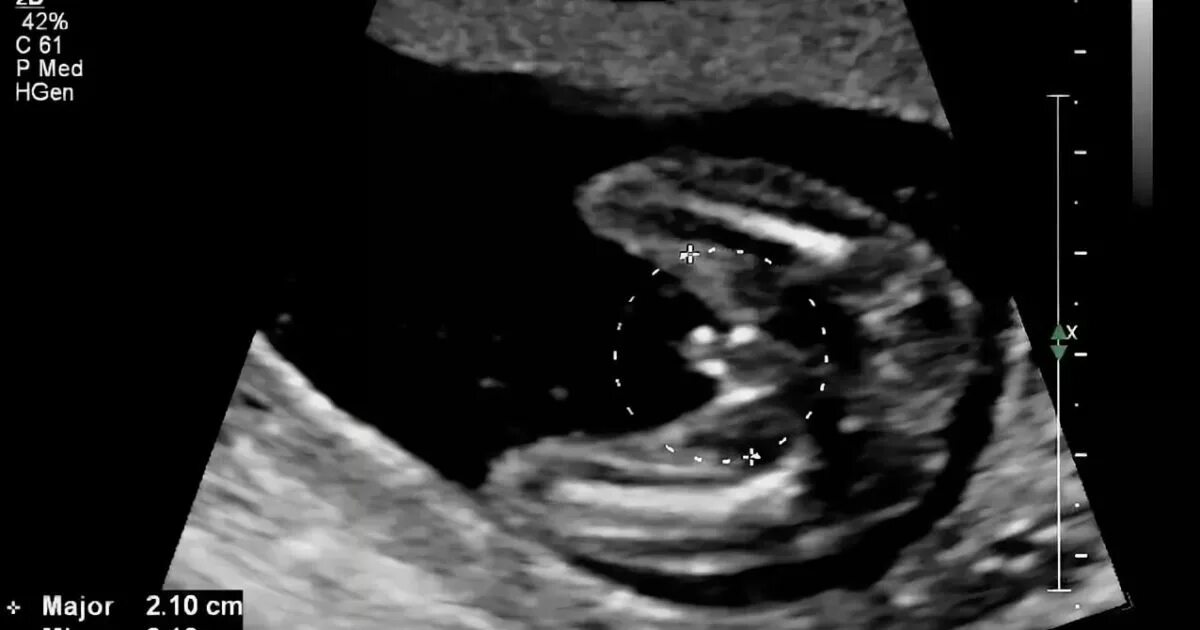

Может врач ошибиться с полом ребенка